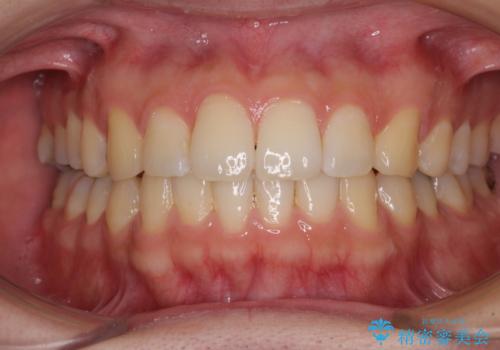

気になるデコボコとオープンバイト インビザラインでの矯正治療

- 前歯のデコボコと上下が開いていることを気にして来院された患者様です。

いわゆるオープンバイトは、インビザラインによる治療が適しているため、インビザラインにて治療を行うこととしました。

オープンバイトは容易に後戻りを起こすため、少しでも後戻りリスクを軽減するために舌癖改善のトレーニングをしっかりと行っていただきました。